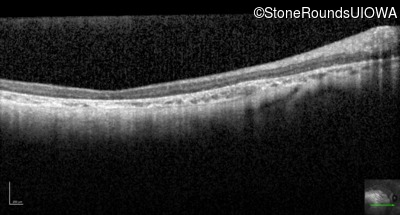

Optical Coherence Tomography - Left - 10/200 sc

Exemplar / OCT Stack

OCT Stack